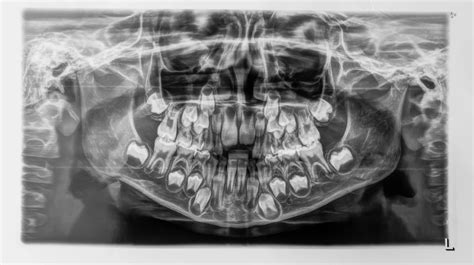

- Se detecta por ortopantografía.

Siempre tendrá que ser valorado por el dentista. Lo habitual es que se realice una prueba de imagen como la ortopantografía. Según su sospecha, puede solicitar otras pruebas de imagen. En función de la causa, el especialista decidirá qué actitud terapéutica será la más adecuada: en algunos casos se recomendará mantener el diente de leche y, en otros, se recomendará su extracción.